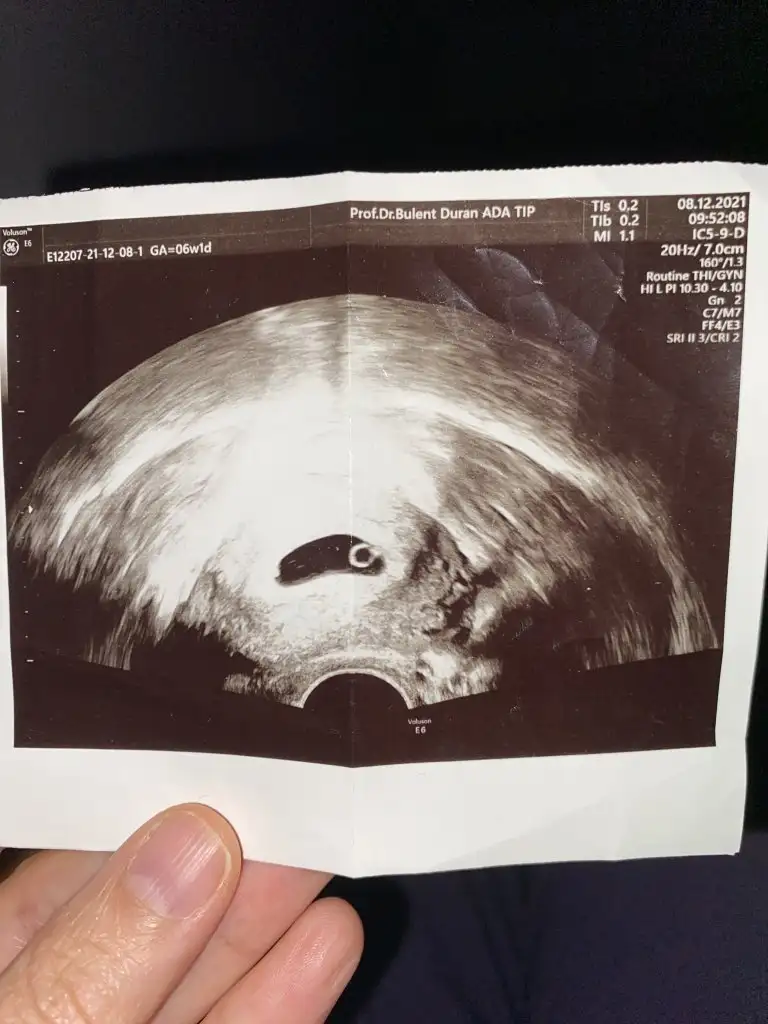

Gebeliğin yine 6-7. haftalarında ki vajinal ultrason ile bebeğin konumuna göre cinsiyet tahmini yapılıyor. Bebek sağda ise erkek , sol yada sol tarafa yakın sa bebek kız demekmiş.

Burda yazılana göre seninki de benimki de kız 😂 vajinalde seninki baya yuvarlak birde kese bak bende vajinal görüntümü atıyorum. Şimdi

Eğer o siyah kısım rahim ise içindeki beyaz şey bebek ise ikimizin de erkek oluyor. Çünkü sağ tarafta. 🙄 ben mi yanlış anladım bilmiyorum 😂